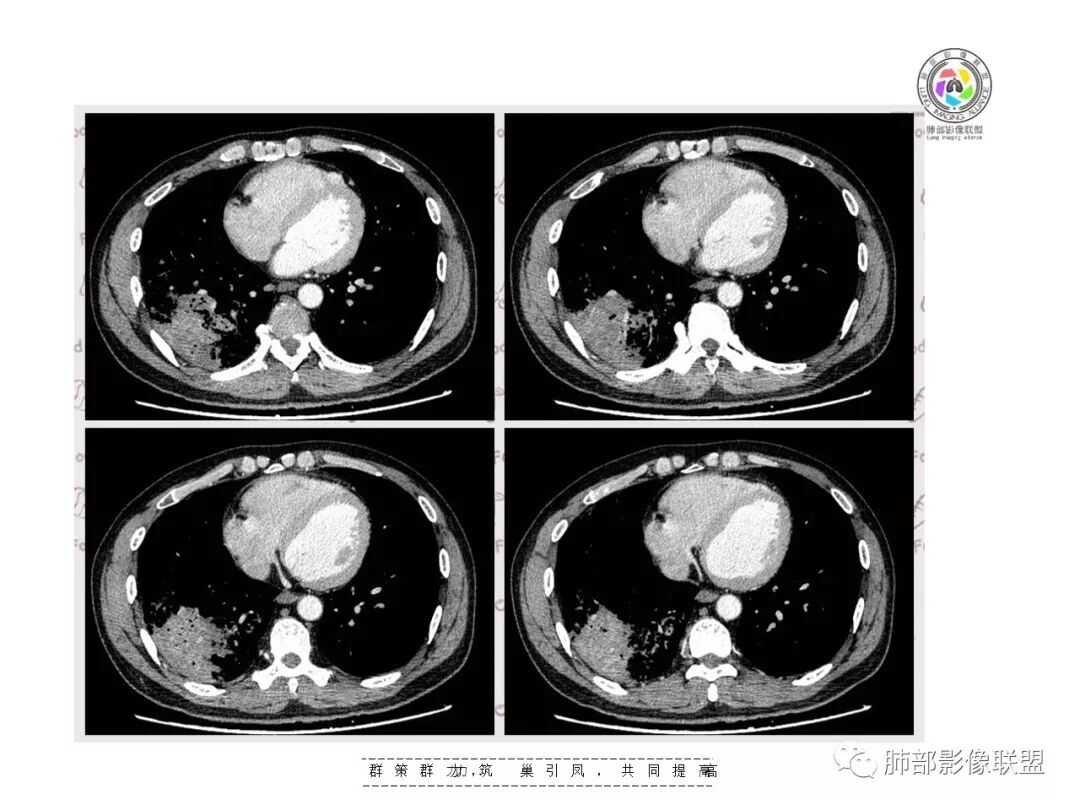

复查胸部CT视频显示肺部病灶明显吸收,淋巴结较前缩小。

患者在本院做了支气管镜,报告是有新生物,取了活检就转院了。病理结果是后来出来的。去肿瘤医院再做支气管镜,病理还是炎症。抗炎治疗(电话追问患者家属,具体不详)一个月后复查,右下肺病变基本吸收,肺门肿块明显变小;纵隔淋巴结基本都没了或者明显变小了

一个月吸收,不是快,是慢,合并机化可能。结核肯定不是。只是觉得你们早上不看病史。有点不好,至少抗感染复查。

现在看树雾,支原体有可能。只是淋巴结肿大和体重减低有迷惑性

如果TB不可能吸收这么快

对,支原体要考虑

淋巴结同步缩小了,其实挺常见的